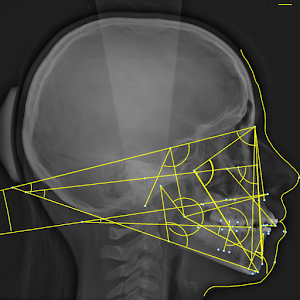

4 renseigner les points

3 analyses à ce jour :

- Analyse C.E.T.O.

- Analyse RICKETTS

- Analyse TWEED